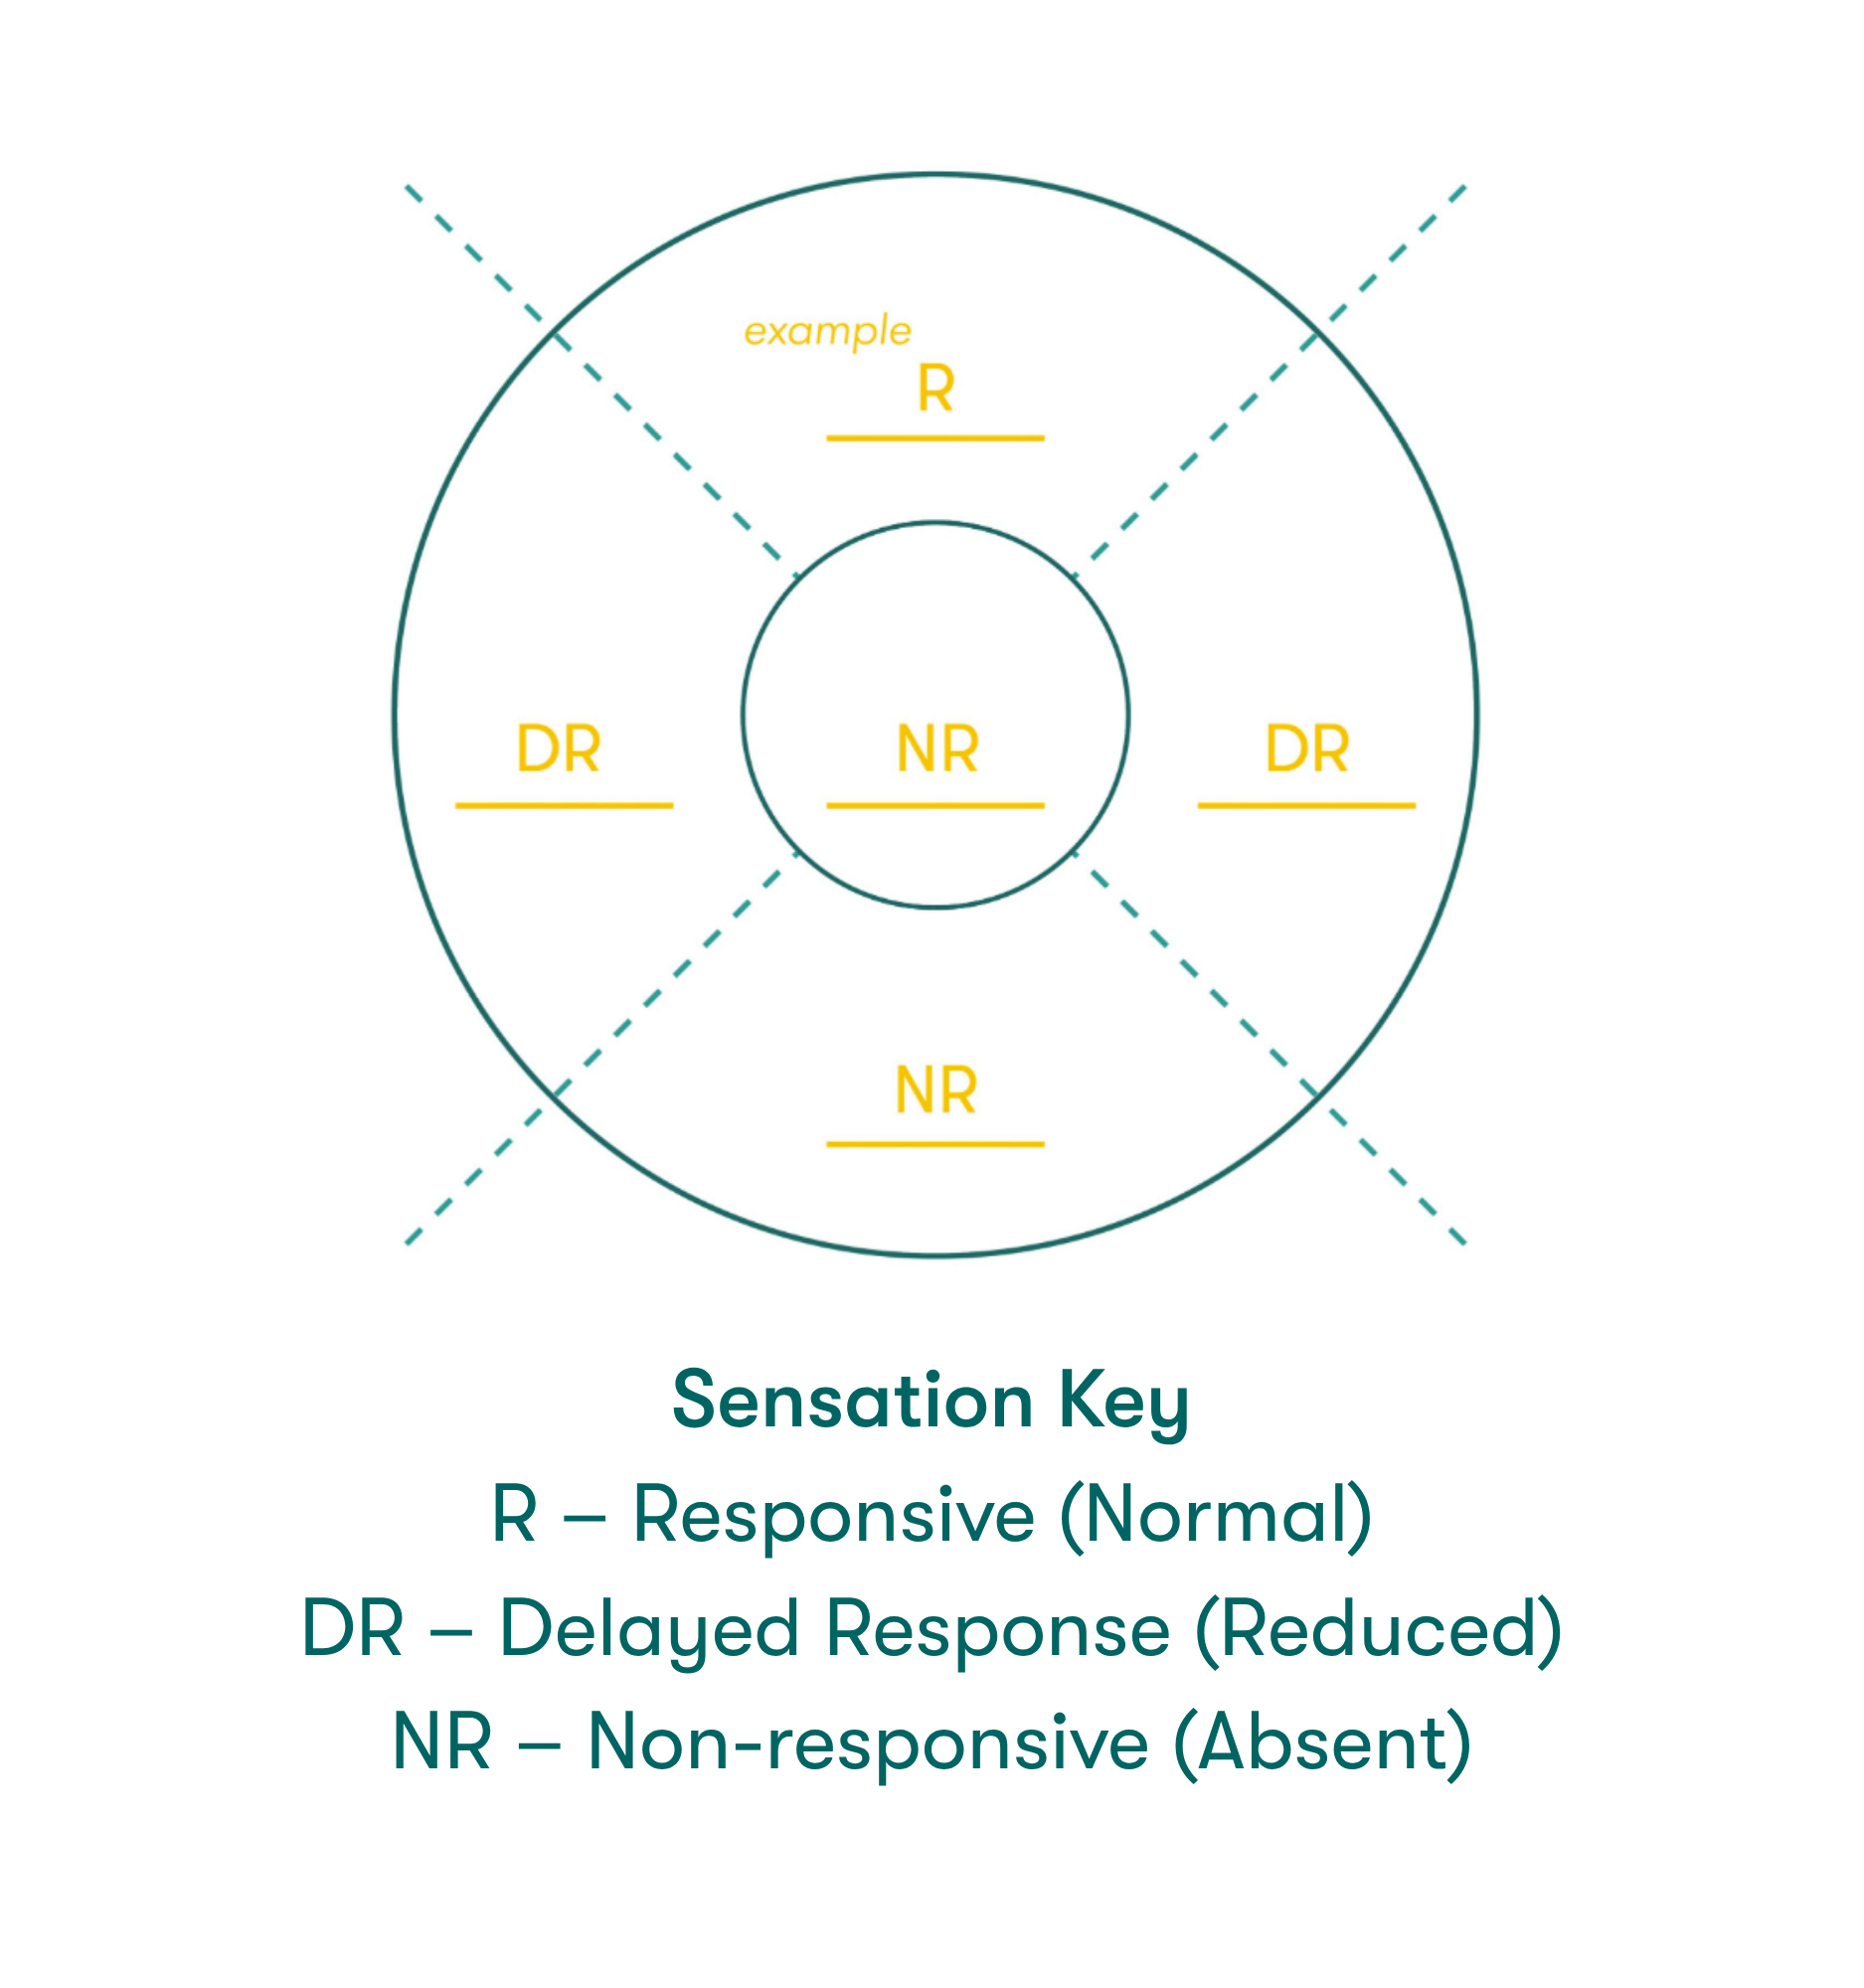

Corneal sensitivity testing can help confirm the diagnosis of NK & assess the severity of corneal nerve impairment. Corneal sensitivity can be measured in two ways:1

- Qualitatively, by touching the central & peripheral cornea with a cotton thread or un-waxed & unflavored dental floss

- When the thread or floss gently touches the cornea, patients with a normal cornea show a blink reaction and can describe the sensation of touch, while patients with loss of corneal sensitivity do not react

- Quantitatively, using a corneal aesthesiometer

The Sensation Key graphic on the right can be labeled with level of sensation to help with disease diagnosis.